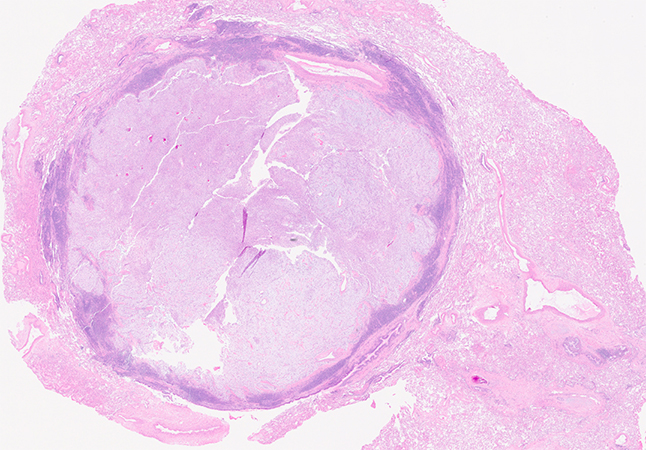

Clinical History: A middle-aged woman with never smoking history complained of chest pain and underwent a chest CT scan. She has no relevant past medical or familial history and no significant environmental exposure. An incidental, solitary 1.5 cm round nodule was found in the periphery of the left upper lobe of lung. A left upper lobe wedge resection was performed for diagnostic and treatment purposes. On gross examination, the nodule measured 1.4 cm, was well-circumscribed and had a pink-tan coloration. Representative histologic images are shown in figures 1 to 4 (figure 1 at 2X, figure 2 at 4X, and figures 3 and 4 at 10X). Figure 5 is a representative image of the AE1/AE3 immunohistochemical stain.

Grossly, pulmonary myxoid sarcomas measure between 1.5 and 14 cm, are well-delineated and nearly always found in relation to an airway. Under the microscope, they frequently show at least a partial fibrous pseudocapsule with a lymphoplasmacytic component. The tumor is frequently lobulated and is composed of spindle/stellate to round cells arranged in cords within a myxoid stroma. Cellularity is variable and cellular areas within a collagenous stroma can be seen. Mitotic count is usually low. Most tumors are cytology bland, but some cases have been reported with atypia, necrosis, and higher mitotic count. By immunohistochemistry, there is no specific diagnostic marker. These tumors are consistently negative for keratins, S100, neuroendocrine markers, desmin, TTF1, and CD34. Some cases are positive for EMA and most are vimentin positive. Immunohistochemistry is mostly useful to rule out other diagnoses included in the differential (Question 4).